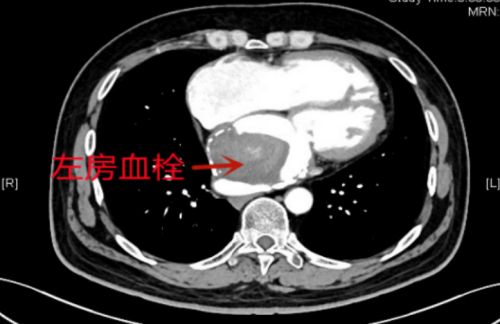

检查结果令人震惊,刘云生不仅患有风湿性二尖瓣狭窄、心房颤动,更严重的是他的左心房内存在一个直径达7厘米的巨大血栓。这个血栓如同一个随时要爆炸的炸弹,时刻威胁着他的生命安全。胸外科、心脏大血管外科副主任、主任医师杨继承向家属解释了这个血栓的危险性:“一旦血栓成分脱落,形成栓子并随血液流向脑血管,就可能引发急性脑梗死;同时,它还对体循环和肺循环造成了严重影响,导致病人的活动能力大幅下降。”

面对如此复杂的病情,杨继承迅速组织多学科专家团队进行深入讨论。经过全面评估,专家们决定为刘云生实施外科手术。手术当天,在体外循环的辅助下,刘云生的心脏暂时停止了跳动。医生们切开右心房和房间隔,打开了左心房,一个直径约7厘米的巨大血栓赫然在目。由于形成时间较长,血栓已经机化,血栓与左房壁紧密粘连,形如一个巨大的“泥球”。长期的血栓刺激还导致左心房内膜形成了一层厚厚的纤维硬壳,进一步损害了左心房的功能。